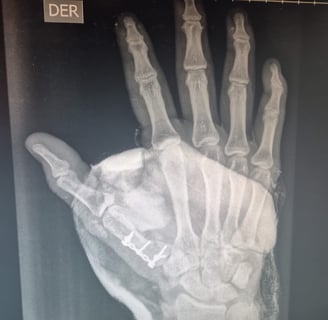

Galería

Imágenes de atención médica y tratamientos quirúrgicos destacados.